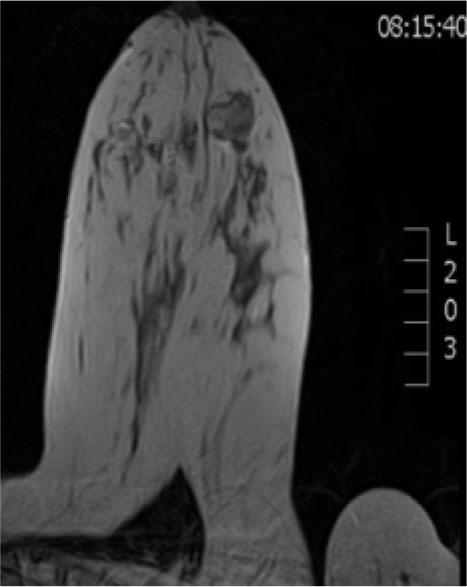

We present the case of a 30-year-old patient in good general condition who noted a fast-growing, painless, clearly limited mass in her left breast. She had no other symptoms, no comorbidities and no data on trauma. Also, she had regular menstrual cycles, did not give birth and no family history of breast cancer. Anamnestic without other ailments and comorbidities, she did not give birth, regular menstrual cycles, no data on trauma, negative family history of breast cancer. The previous ultrasound examination peformed a year ago was unremarkable. Clinical examination revealed a palpabile formation measuring about 3 cm without significant axillary lymphadenopathy. Ultrasound examination detected a lobulated tumor mass dimension 35x28x11mm, heteroechoic structure, horizontally oriented with few oval shaped axillary lymph nodes up to 9 mm, mostly like reactive type, which is classified as BIRADS 4a (Figure 1).

Ultrasound axial plane showing lobulated, heteroechoic tumor mass